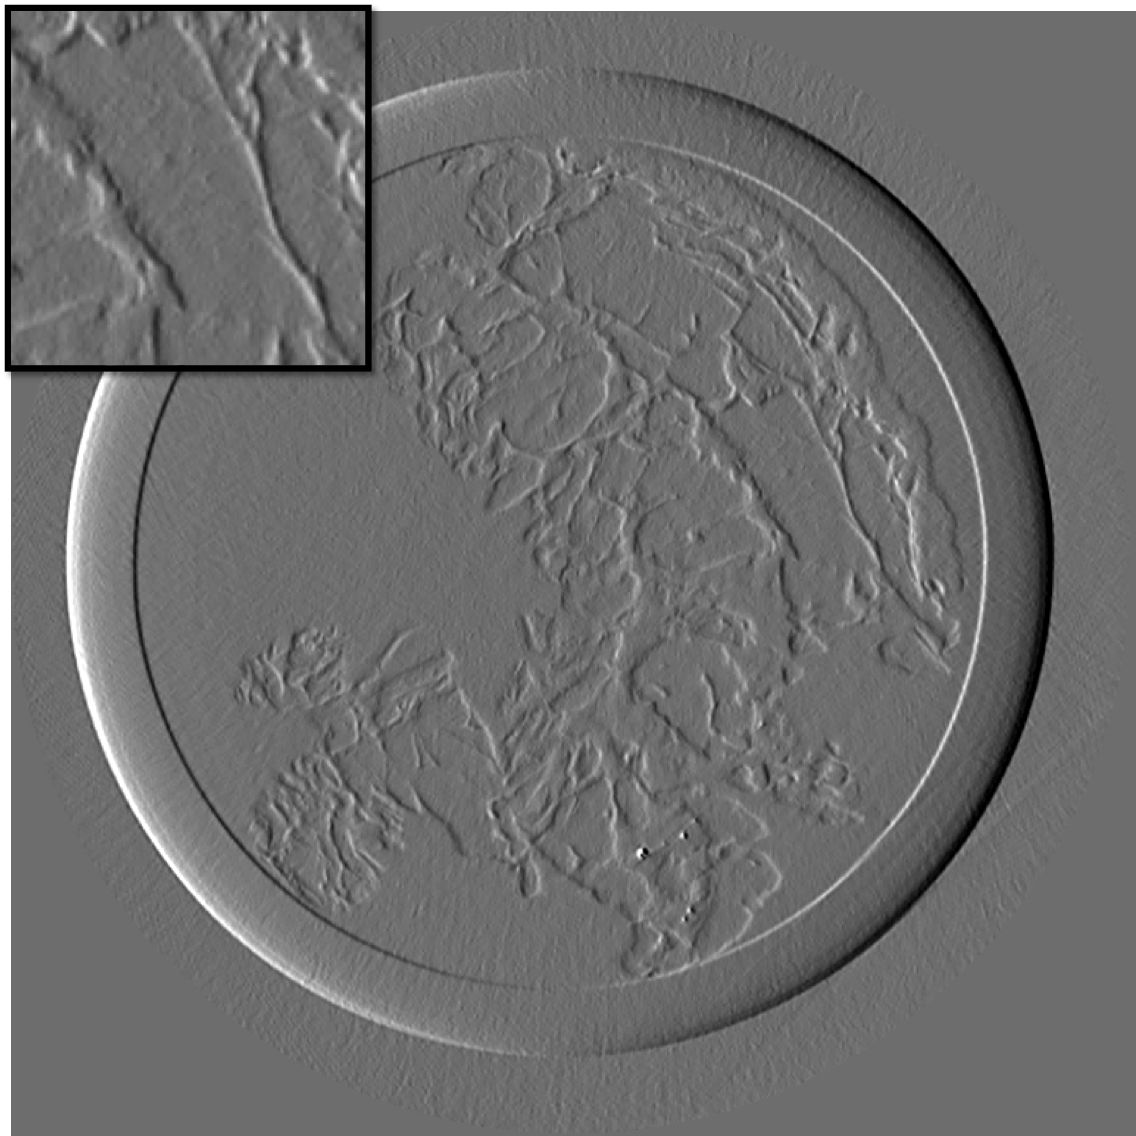

Figure 10 is the reconstruction for a pixels slice, using only 200 projections over the 1000 available. The upper left square is a zoom in the region marked in sub figure 10. The right column is the reconstruction with our method for X and Y components, while the left column is reconstructed with standard filtered back-projection using all 1000 available projections. Using our method we can still generate a high quality image with only one fifth of the projections which would be otherwise necessary to generate a high quality reconstruction with the standard FBP method. Visually the difference between the FBP results obtained with full data set and our method with a five-fold reduction of data is barely noticeable. The different borders of structures like skin layers, fatty tissues, and collagen strands are easily identified. The obtained result are very promising and a systematic evaluation for clinical application is under-way. The radiation dose absorbed by the sample during 200 projections is comparable to that of a standard clinical dual view (2D) mammography (3.5mGy).

For an eventual future clinical application of the PCI method it is important to investigate which is the acceptable compromise in terms of low dose and sufficient level of image quality. We need therefore to better explore how the quality of the reconstruction is degraded when we reduce the dose (i.e. number of projections and the acquisition time) further below the standard values. To this end, we performed a reconstruction with only 125 projections and results are shown in the figure III-D for one gradient differential image.

For an eventual future clinical application of the PCI method it is important to investigate which is the acceptable compromise in terms of low dose and sufficient level of image quality. We need therefore to better explore how the quality of the reconstruction is degraded when we reduce the dose (i.e. number of projections and the acquisition time) further below the standard values. To this end, we performed a reconstruction with only 125 projections and results are shown in the figure11. The first column present the result using our method, the second column is the result of reconstruction using FBP algorithm.

If a slightly higher noise level is tolerable, the method may be used with very few projections and thus applied to the screening and diagnosis of human breast cancers with an even lower radiation dose than conventional dual mammography. The results of our reconstruction show an image quality and a capability of discriminating fine structures that are still clinically acceptable. On the contrary, images produced with the standard FBP reconstruction method are very noisy and not diagnostically satisfactory.